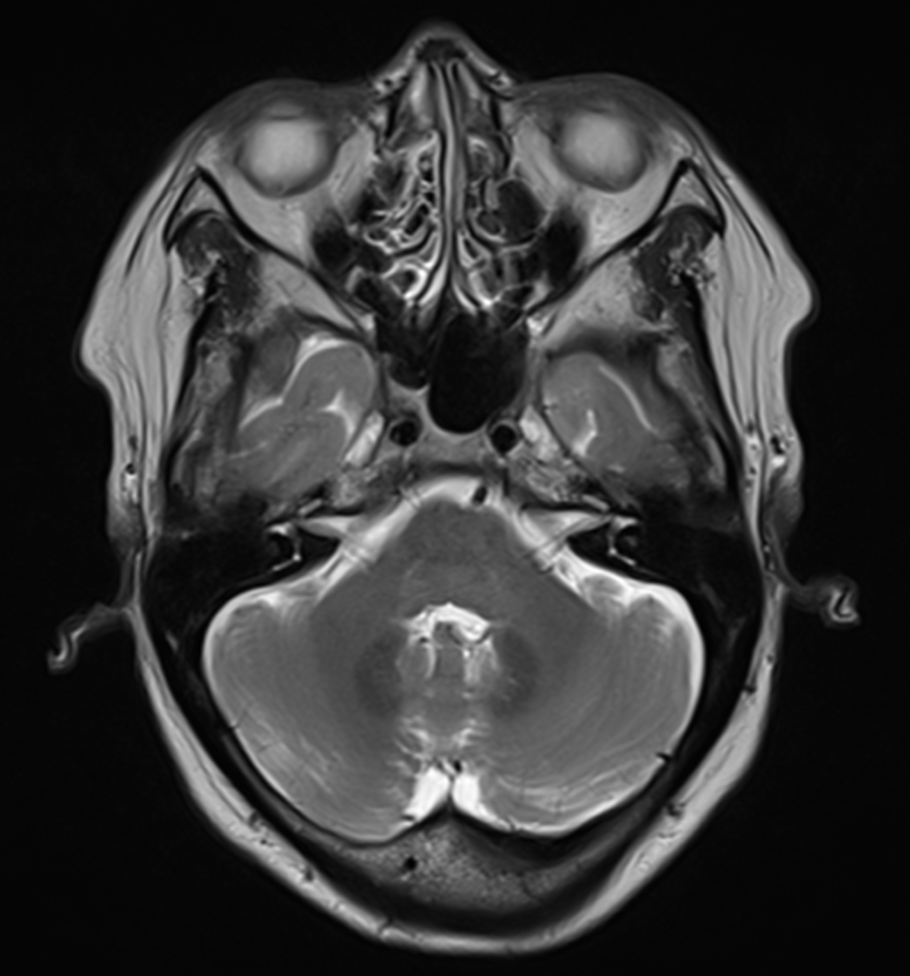

그림10.png 촬영 일시: 2025.07.01

<Fig 1. 뇌 MRI>

검사 결과를 보는 순간...

역시나 제 예상이 맞았습니다.

3차신경에 뚜렷한 염증 소견이 보였어요.